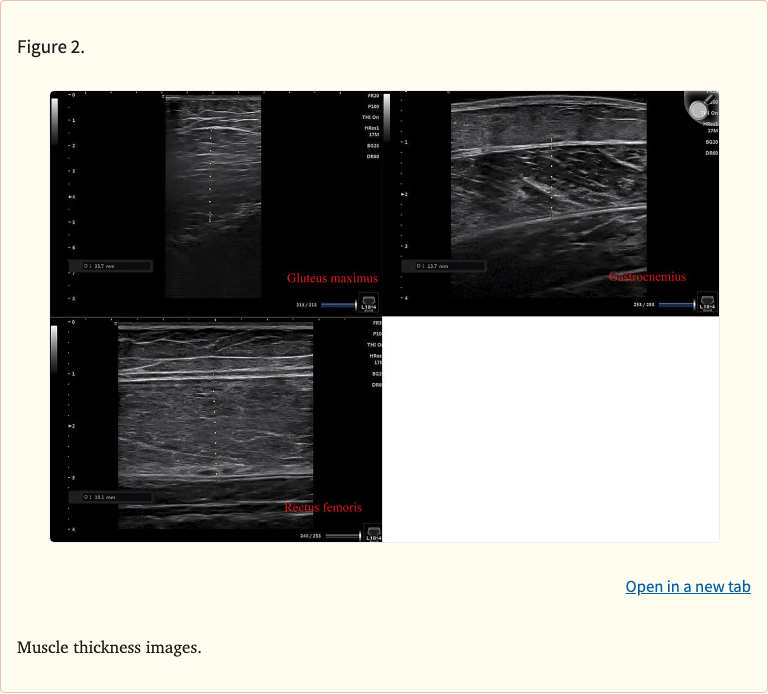

Both groups trained 3 times per week for 8 weeks. Muscle thickness of the quadriceps was measured via ultrasound, isokinetic peak torque assessed knee extensor strength, and body composition was evaluated using bioelectrical impedance analysis.

• Outcomes: quadriceps muscle thickness (ultrasound), isokinetic peak torque, body fat percentage (BIA)

• Both groups significantly increased quadriceps muscle thickness (no significant between-group difference)